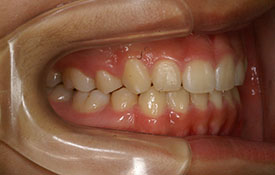

インビザラインの治療例:CASE-2

| プロフィール | 15歳 男性 |

| 所見 | アメリカから転院されて来られた方です。 インビザラインで上下顎の矯正治療を開始し下顎はアメリカで終了しており、上顎のみ治療の後期を担当しました。 アイライナーの装着は、1日平均22時間ほどでした。 |